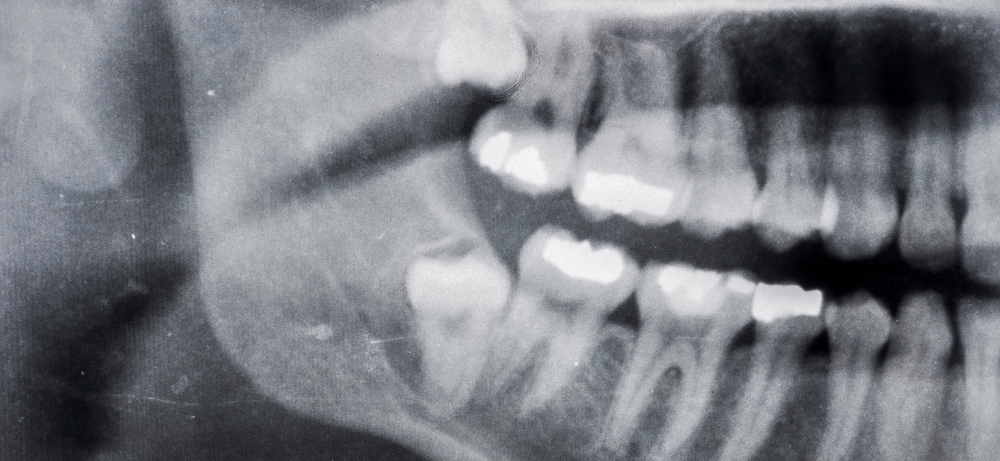

Trångboddhet uppstår – Eftersom käken inte erbjuder tillräckligt med utrymme för att visdomständerna ska kunna bryta fram ordentligt. Detta kan leda till att tänderna fastnar eller växer ut i fel vinkel, vilket kan skada närliggande tänder eller orsaka betydande obehag.

Tanden växer snett – Om dina visdomständer växer snett kan det orsaka trångboddhet genom att de trycker mot dina andra tänder. Detta kan inte bara leda till felställda tänder utan också öka risken för smärta, tandköttsinflammation samt svårigheter att upprätthålla god munhygien, vilket i sin tur ökar risken för karies och tandköttsproblem.

Inbäddade visdomständer – Visdomständer som inte kan bryta igenom tandköttet eller som är helt dolda inom käkbenet, gör dem extremt svåra att rengöra och ökar risken för att problem ska uppstå.